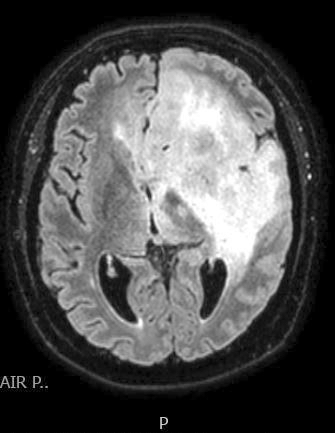

Radiology description

- CT:

- Expanding, intra-axial, poorly defined mass of low density

- Variable calcification may be seen

- Contrast enhancement and central hypodensity due to necrosis, occur with higher grades

- MRI:

- T1 hypodensity and T2 hyperintensity

- T2 hyperintensity with relative FLAIR sequence hypointensity (T2 FLAIR mismatch) is a relatively suggestive indication of IDH mutant astrocytoma (Clin Cancer Res 2017;23:6078)

- Distortion and enlargement of involved areas, including associated cortical ribbon

- Contrast enhancement is typically present in higher grade tumors (J Neurooncol 2019;141:327)

- Ring-like enhancement around central necrosis typical of grade 4

Radiology images